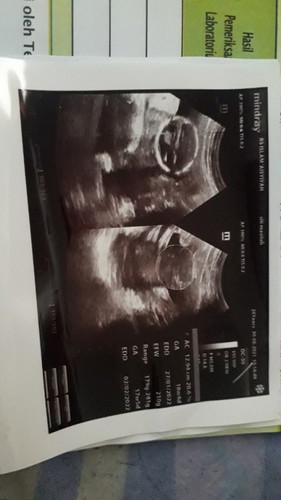

Bun, ada gg yg sm ky sy setiap pergantian minggu pasti ajj kumat mulmunnya, trkdng smpai sakit, dan dada terasa nyeri. Pdhl sdh memasuki UK 19W. Smpai2 badan habis krna mulmun, hmil anak pertama sangat khawatir, bln lalu USG Di bilng BBJnya kurang. Jd nmbh pikiran. Smpai skrng blm priksa lagi. Kira2 apa ajj yh yg hrs saya tanyakan saat USG nnti, dn tidak apa2 kan klw kita setiap blnnya USG? TERIMAKASIH DAN SEMOGA IBU2 YG SDNG MRASAKAN SPRTI SAYA SELALU SEHAT IBU DAN DEDE BAYINYA 🙏🏻😊 #pleasehelp